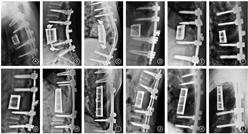

根据不同病变节段和病椎形态进行个性化设计,上下终板前后径、左右径和上下终板角度均与患者椎体缺损形成个体化匹配。人工椎体采用多孔结构和实心桁架相结合的结构提升人工椎体的力学强度。椎体中央设计植骨孔道,椎体背面为光滑结构避免与硬膜粘连,椎体两侧设计有可供夹持和术中调整的夹持孔(图1)。采用激光选区熔融的工艺进行加工,加工后进行后处理、清洗和灭菌消毒,备术中使用。

术后随访6个月按Brantigan-Steffee的影像学融合标准判定为全部融合(图2),融合有效率为100%[95%CI(75.6%,100%)],95%CI下限大于预设目标值70%,人工椎体产品的有效性满足临床要求。